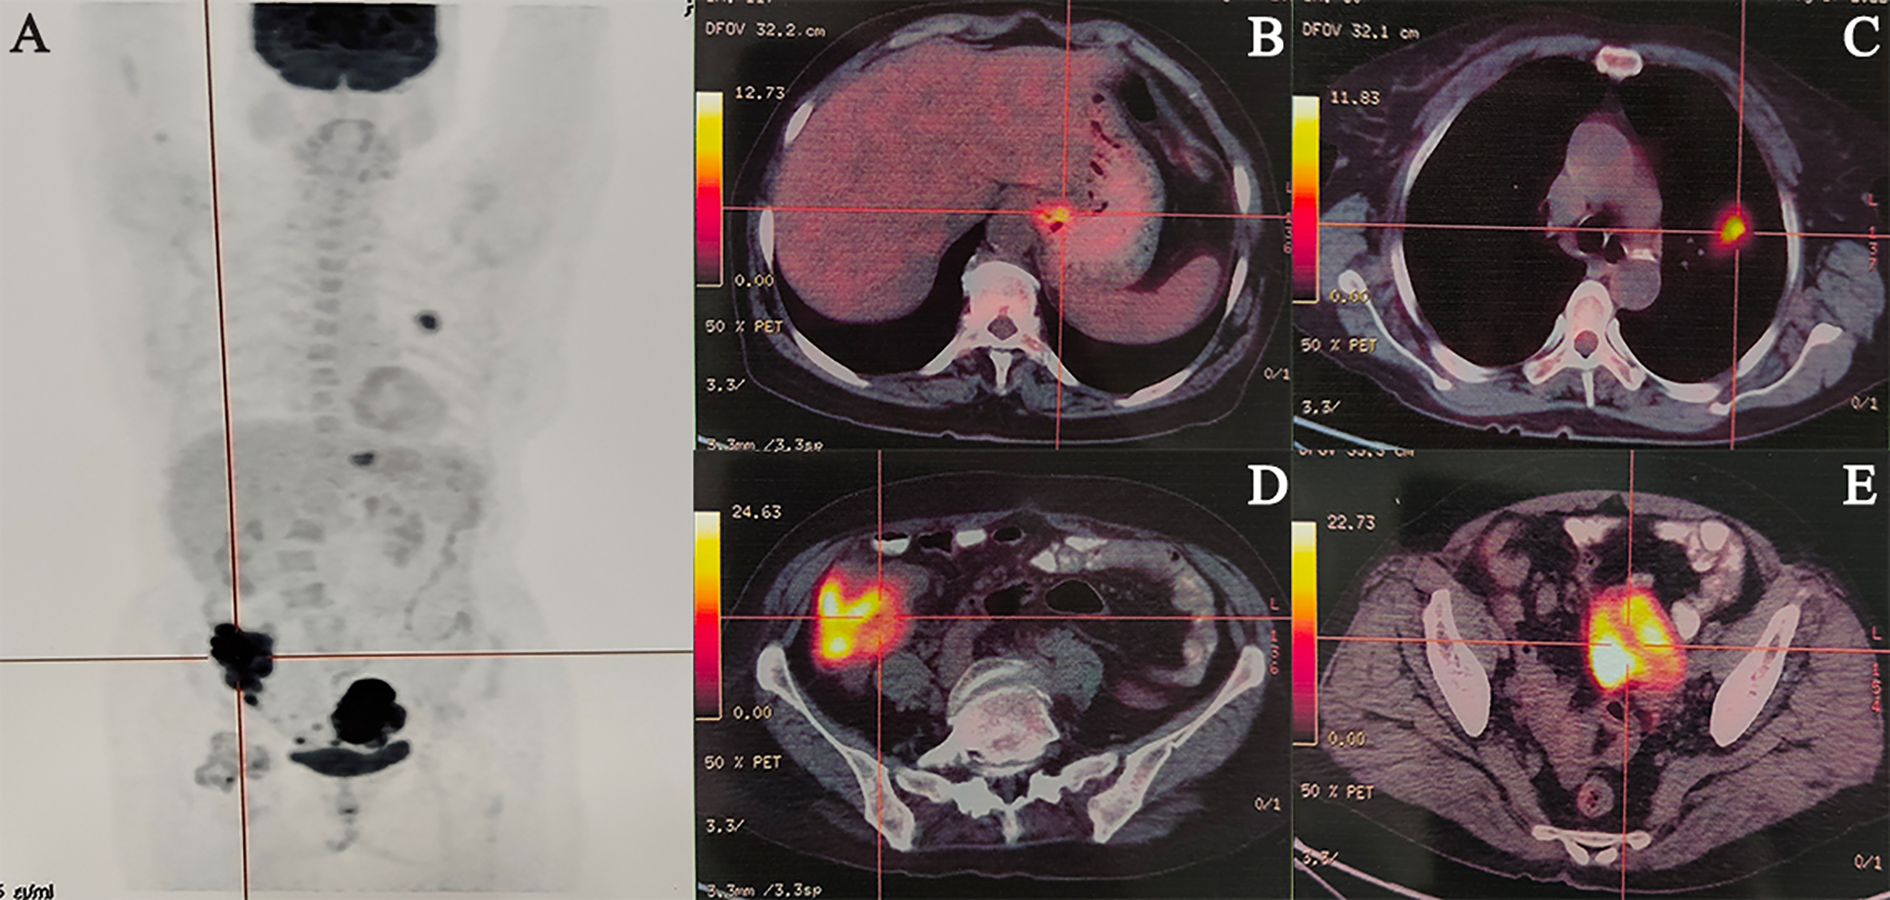

An abdominal computed tomography (CT) scan performed on May 3, 2022, identified a mass in the ascending colon (Figure 1A). A subsequent colonoscopy (May 5, 2022) and pathological biopsy confirmed moderately differentiated adenocarcinoma (Figure 1B). The patient was admitted for surgical evaluation. Preoperative workup revealed additional masses in the left ovary and left lung, as well as gastric wall thickening at the cardia. Imaging features were inconsistent with metastatic disease. Positron emission tomography-computed tomography (PET-CT; Figure 2) demonstrated the following: 1.Hypermetabolic thickening in the ileocecal region, consistent with colorectal cancer; 2. A hypermetabolic soft tissue mass in the left pelvis, consistent with a primary pelvic tumor; 3. A hypermetabolic nodule in the apical-posterior segment of the left upper lung, consistent with invasive lung adenocarcinoma; 4. Hypermetabolic thickening of the gastric wall at the cardia, suspicious for gastric adenocarcinoma.

Figure 2

Representative cases of malignancies. (A) Maximum Intensity Projection, (B) Gastric cardia cancer, (C) Left lung cancer, (D) Colon cancer, (E) Ovarian cancer.